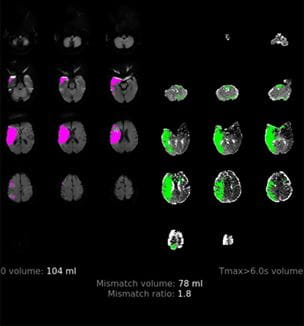

Global SELECT2 Clinical Trial Studies Endovascular Thrombectomy in Large Core Infarct Patients

Innovations in Neurology & Neurosurgery | Summer 2022